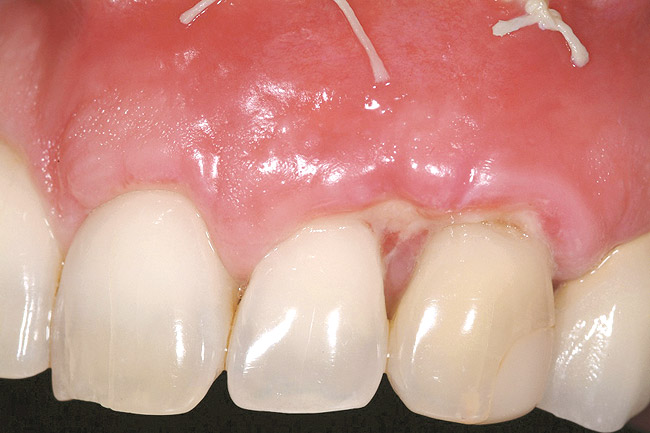

The 2.5-week postoperative clinical view can be seen in Figure 10 through Figure 12. Note the rapid soft tissue healing and maturation. At 6-weeks postoperative, tissue plasty was accomplished to blend the thickened keratinized tissue, in addition to placement of class V composite restorations at teeth Nos. 5, 6, and 11 to create a new restorative margin on the root surfaces.

The 2-month postoperative view can be seen in Figure 13 through 15. Note the color match of the tissue, balance of the facial heights of contour, and zones of attached keratinized tissue present.

Figure 10  Case One The 2.5-week postoperative view, maxillary anterior.

Figure 10

Figure 11  Case One The 2.5-week postoperative view, maxillary right.

Figure 11

Figure 12  Case One The 2.5-week postoperative view, maxillary left.

Figure 12